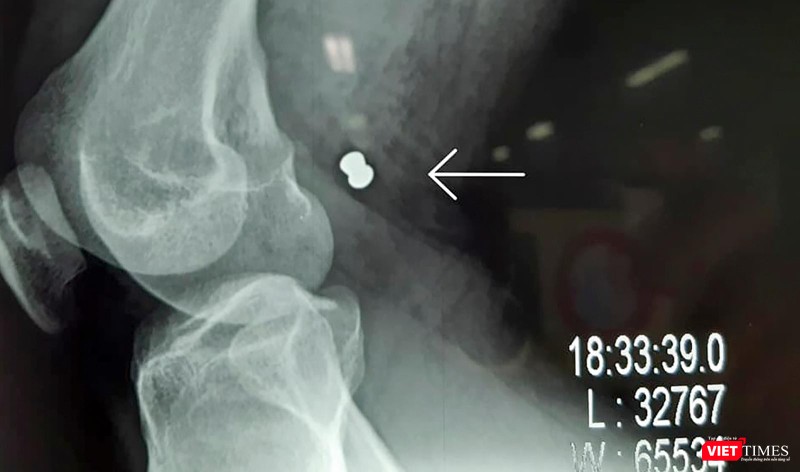

Sau khi siêu âm, chụp X-quang, bác sĩ xác định trong đùi phải anh H. có viên đạn, khả năng làm tổn thương các mạch máu nên phải phẫu thuật khẩn cấp.

Sau khi tiến hành hội chẩn, êkíp bác sĩ bệnh viện đã phẫu thuật cấp cứu cho bệnh nhân liên tục trong vòng 5 tiếng đồng hồ và truyền 4 đơn vị máu (khoảng 1,5 lít) mới đưa được viên đạn ra ngoài. Sau khi phẫu thuật, sức khoẻ bệnh nhân đã ổn định và hồi phục.